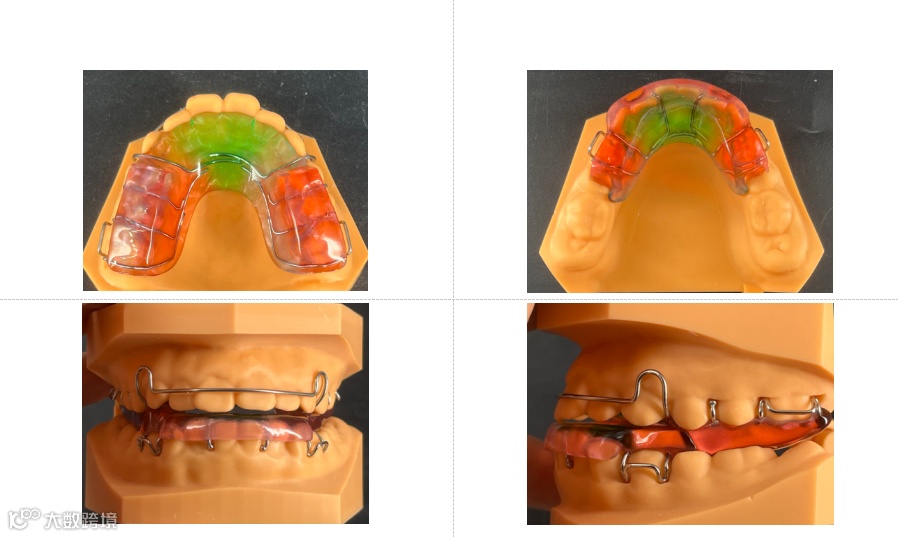

Twin block矫治器组成:

由上下颌两部分活动矫治器组成。

由位于第一磨牙的箭头卡、位于第一、二前磨牙或第一、二乳磨牙间的邻间钩、双曲唇弓、基托斜导面组成。

箭头卡及邻间钩起固位作用,双曲唇弓用于内收angle ll 1分类前凸的上前牙,也有部分的固位作用;安氏二类2分类的患者可在前牙舌侧放置舌簧。

由位于第一前磨牙的箭头卡、位于下前牙的邻间钩(两个或三个)、基托斜导面组成。

下颌的箭头卡一般位于第一前磨牙,对于后期需要调磨上颌颌垫而使下颌后牙伸长的病例来说,当其放置于第二前磨牙或磨牙时,箭头卡跨牙合部分会影响下颌后牙的伸长。

下前牙的邻间钩可防治下切牙的前倾。

下颌导斜面的后缘不向远中越过下颌第一磨牙的近中边缘嵴,以免影响其伸长,同时,其过于靠近远中会影响患者佩戴时的咀嚼效率。

下颌导斜面的上部最好能少量包裹与之对应的上颌牙,以进一步阻止下颌的后退。

前牙切三分之一可被树脂包绕,进一步防止下前牙前倾。